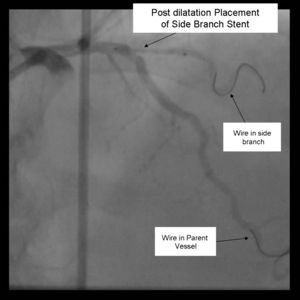

11) Kissing balloons are inflated at the bifurcation. It is sometimes necessary to dilate the sidebranch with a small balloon (1.5 mm middle marker balloon) to facilitate a larger balloon for the kiss.

12) Repeat angiography is performed. Wires are removed and final angiography completed.